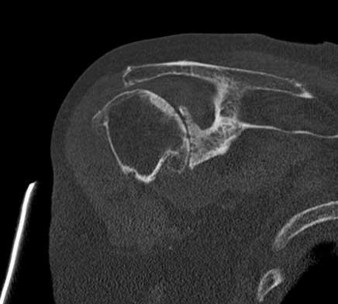

Question 10:

According to recent quantitative anatomical studies utilizing MRI and gadolinium, which of the following vessels provides the principal intraosseous blood supply to the humeral head, challenging historical teachings regarding proximal humerus vascularity?

Correct Answer: Posterior humeral circumflex artery

Explanation:

Historically, the anterior humeral circumflex artery (via its arcuate branch) was thought to be the primary blood supply to the humeral head. However, modern quantitative studies (e.g., Hettrich et al.) have demonstrated that the posterior humeral circumflex artery provides the vast majority (approximately 64%) of the intraosseous blood supply to the humeral head.